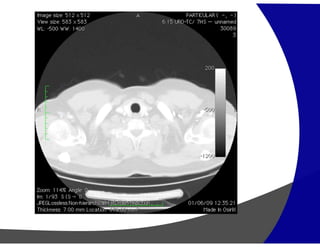

Asbestose:

Manifestações idênticas à FIP. Entretanto, asbestose

deve ser suspeitada quando são vistas placas

pleurais

Asbestose: Manifestações idênticas àFIP. Entretanto, asbestose deve ser suspeitada quando são vistas placas pleurais